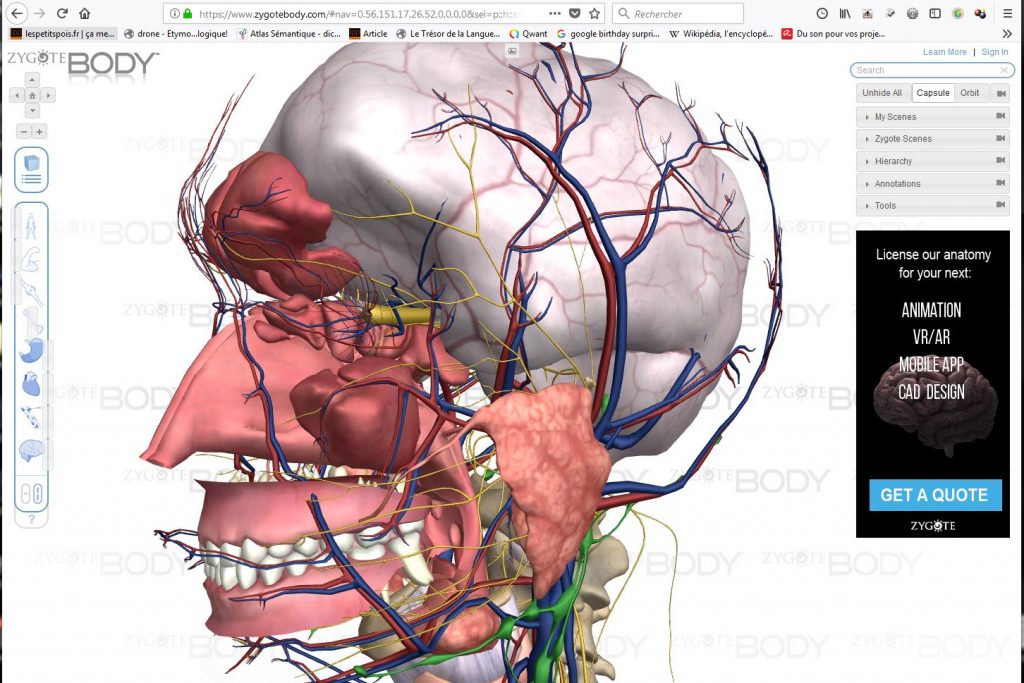

Explorer le corps humain online, c’est possible avec https://www.zygotebody.com. J’y ai passer quelques heures à m’amuser avec ces derniers jours.

Voici quelques pistes pour un bonne manipulation du site:

1/ On peut explorer le corps d’une homme ou d’une femme:

2/ Il y a deux modes de navigation proposés:

la première, par défaut, permet de “déshabiller” le modèle couche après couche en faisant glisser le curseur de haut en bas:

la seconde permet de choisir grâce à plusieurs curseurs, les types de “composant” à cacher et l’intensité de leur visibilité:

3/ Il est bien évidemment possible de zoomer et de tourner autour du modèle, directement avec la souris:

4/ On peut cliquer sur chaque élément pour avoir son nom et éventuellement une explication (en anglais):

5/ On peut même s’amuser à cacher les éléments un par un (puis à les faire réapparaître mais tous en même temps pour le coup):